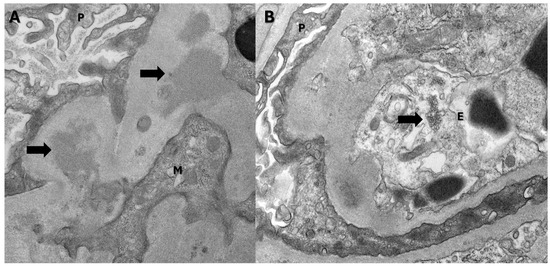

2. Case Presentation